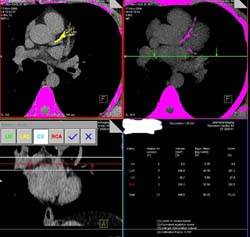

How does cardiac CT work?

With such a fast scanner, it is possible to "freeze"

the heart. The new 64-slice scanner obtains almost

194 slices per second. After gating with the ECG,

it is possible to scan the heart in 10-12 seconds

and to extract information about the coronary arteries

and cardiac function from the dataset.

What are the various parts of the study?

The following 3 parameters are studied

- Calcium scoring

- Coronary artery assessment

- Functional assessment (wall motion and ejection

fraction)